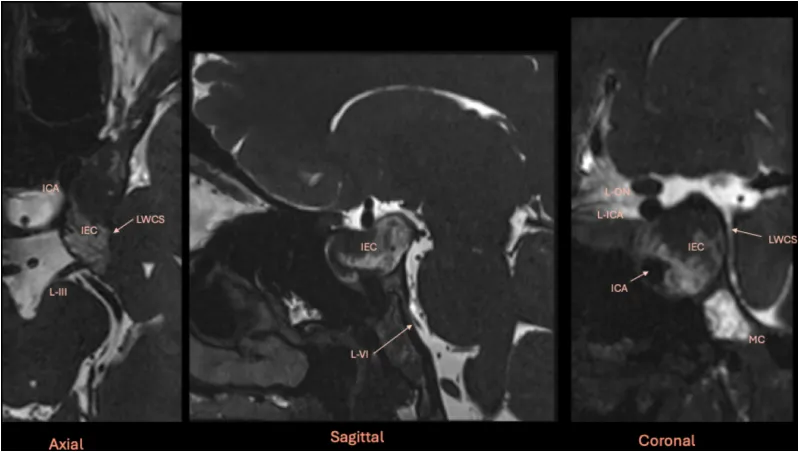

图2:术前多平面磁共振成像CISS序列研究。纯海绵窦内表皮样囊肿明确位于海绵窦内,将颈内动脉向前内侧推移,并使海绵窦外侧壁(内含左侧动眼神经)向外侧膨出。缩写:ICA:颈内动脉;MC:Meckel腔;L-ON:左侧视神经;L-VI:左侧外展神经。

图3:对侧单鼻孔内镜经鼻入路的术前影像规划。规划使用Carestream Image Suite软件进行,图像在空间上同步。图中蓝色线条指示图像的方位。黄色十字在所有三幅图像中共同配准,用于识别垂体。橙色箭头指示计划的手术路径。囊肿在海绵窦外侧隔腔内、颈内动脉海绵窦段与海绵窦外侧壁之间形成了一个自然的的手术通道。骨窗CT扫描对于理解蝶窦解剖至关重要。在本例中,蝶窦中隔标识了蝶鞍和中线,而较小的左侧间隔附着于左侧颈内动脉隆起。基于此解剖结构,可采用对侧经鼻甲前部入路抵达左侧海绵窦,无需完全蝶窦切开,从而保留了右侧蝶窦。